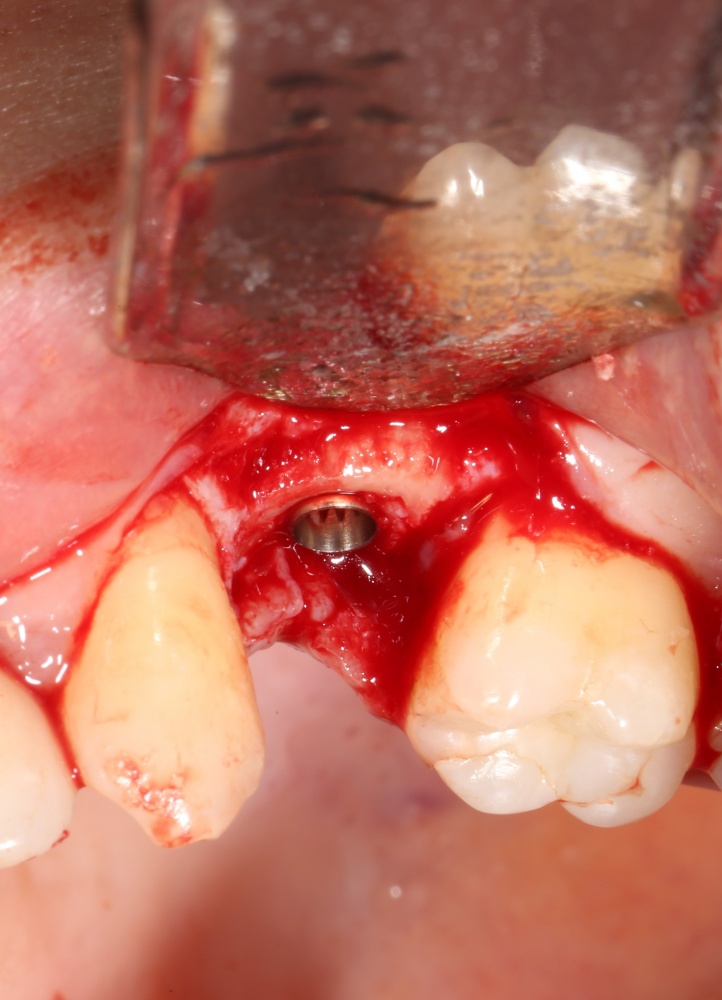

Простой. Надежный. Дешевый. Способ остеопластики.